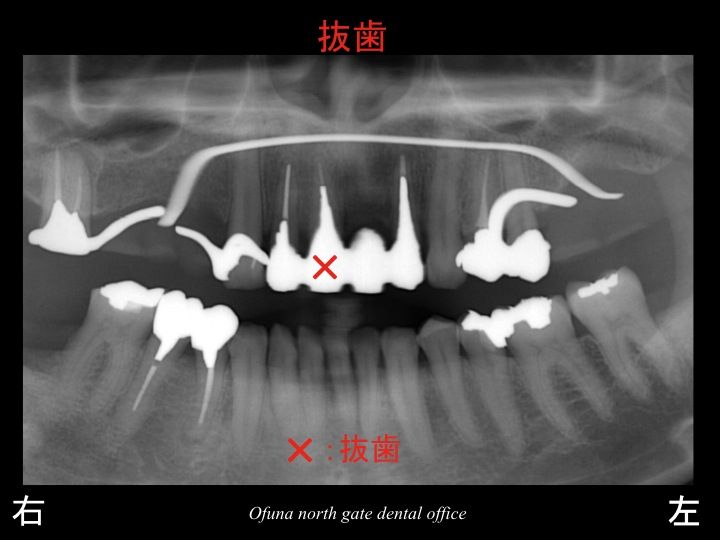

以下の×印が欠損部位です。

上顎は、6歯分欠損しています。

もともと上顎には、14歯分の歯が存在していますので、

半分以上の歯がないことになります。

もし、インプラント治療後に 以下の ×印 の歯がダメになった場合には、

さらに追加のインプラントが必要となります。